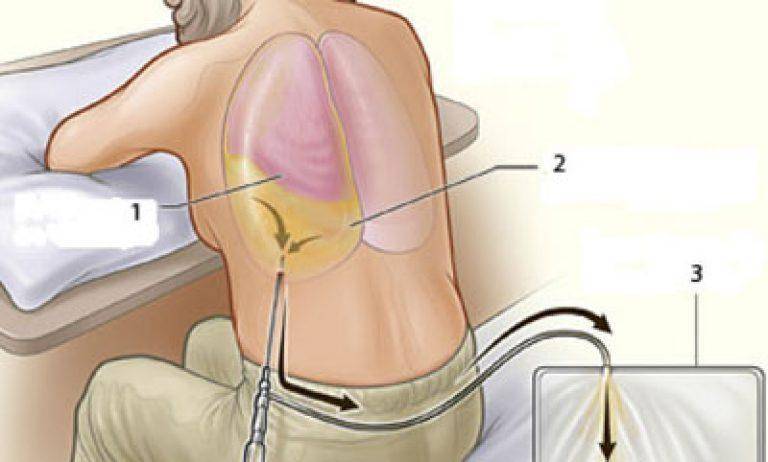

Анатомия межплеврального пространства